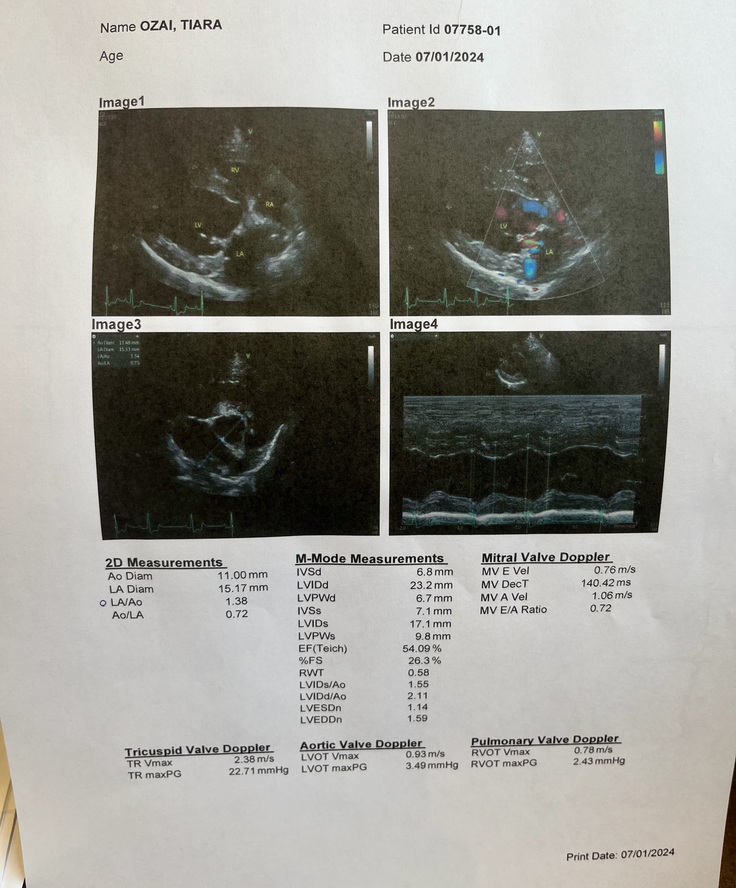

心臓の状態は経過が良く

血液検査はほとんどの数値が基準値内で

レントゲン、エコー、血圧の検査結果から

問題無く順調に回復しておりました✨

心臓もかなり小さくなり

僧帽弁、三尖弁共に軽度の逆流は残るものの

※レントゲン、エコーの写真は

左側が術後で、右側が術前になります。